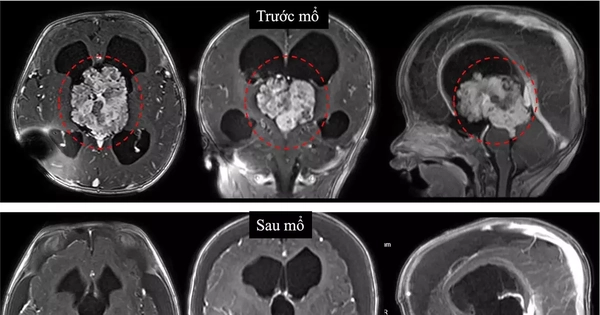

TPO - Ngày 11/4, TS.BS Trần Minh Huy, khoa Ngoại Thần kinh, Bệnh viện Nhi đồng 1 TPHCM cho biết, tại đây vừa điều trị thành công một trường hợp bệnh nhi 7 tháng tuổi mắc khối u não hiếm gặp, nằm ở vị trí rất sâu trong não.